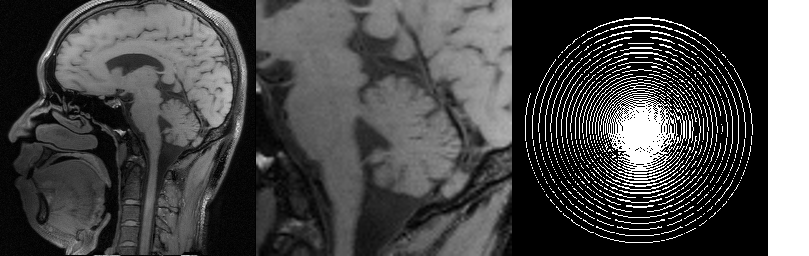

We select a -sized -weighted axial brain scan from our collection along with a 20% Cartesian mask. In order to simulate upright and rotated image acquisition sequences, we consider two setups:

-

1.

The reference image is in upright orientation. The FFT of the image is taken, then the sampling mask is applied (see Fig. 5 (1)).

2.

The reference image is rotated from upright position, say, by (counterclockwise). The FFT is taken, then the sampling mask rotated by the same is applied (see Fig. 5 (2)).

We investigate the performance of RITV compared to TV and TGV in these setups. The implementation of RITV is the same as described in Algorithm 1 and Subsection 3.1, with the only difference being the removal of the BM3D term (and readjustment of to ), since we wish to observe the performance of RITV only. TGV is implemented using the algorithm and parameters described in [7]. TV is also implemented with the same algorithm, with optimized to . TV and TGV algorithms run for 500 iterations while the RITV runs for 200.